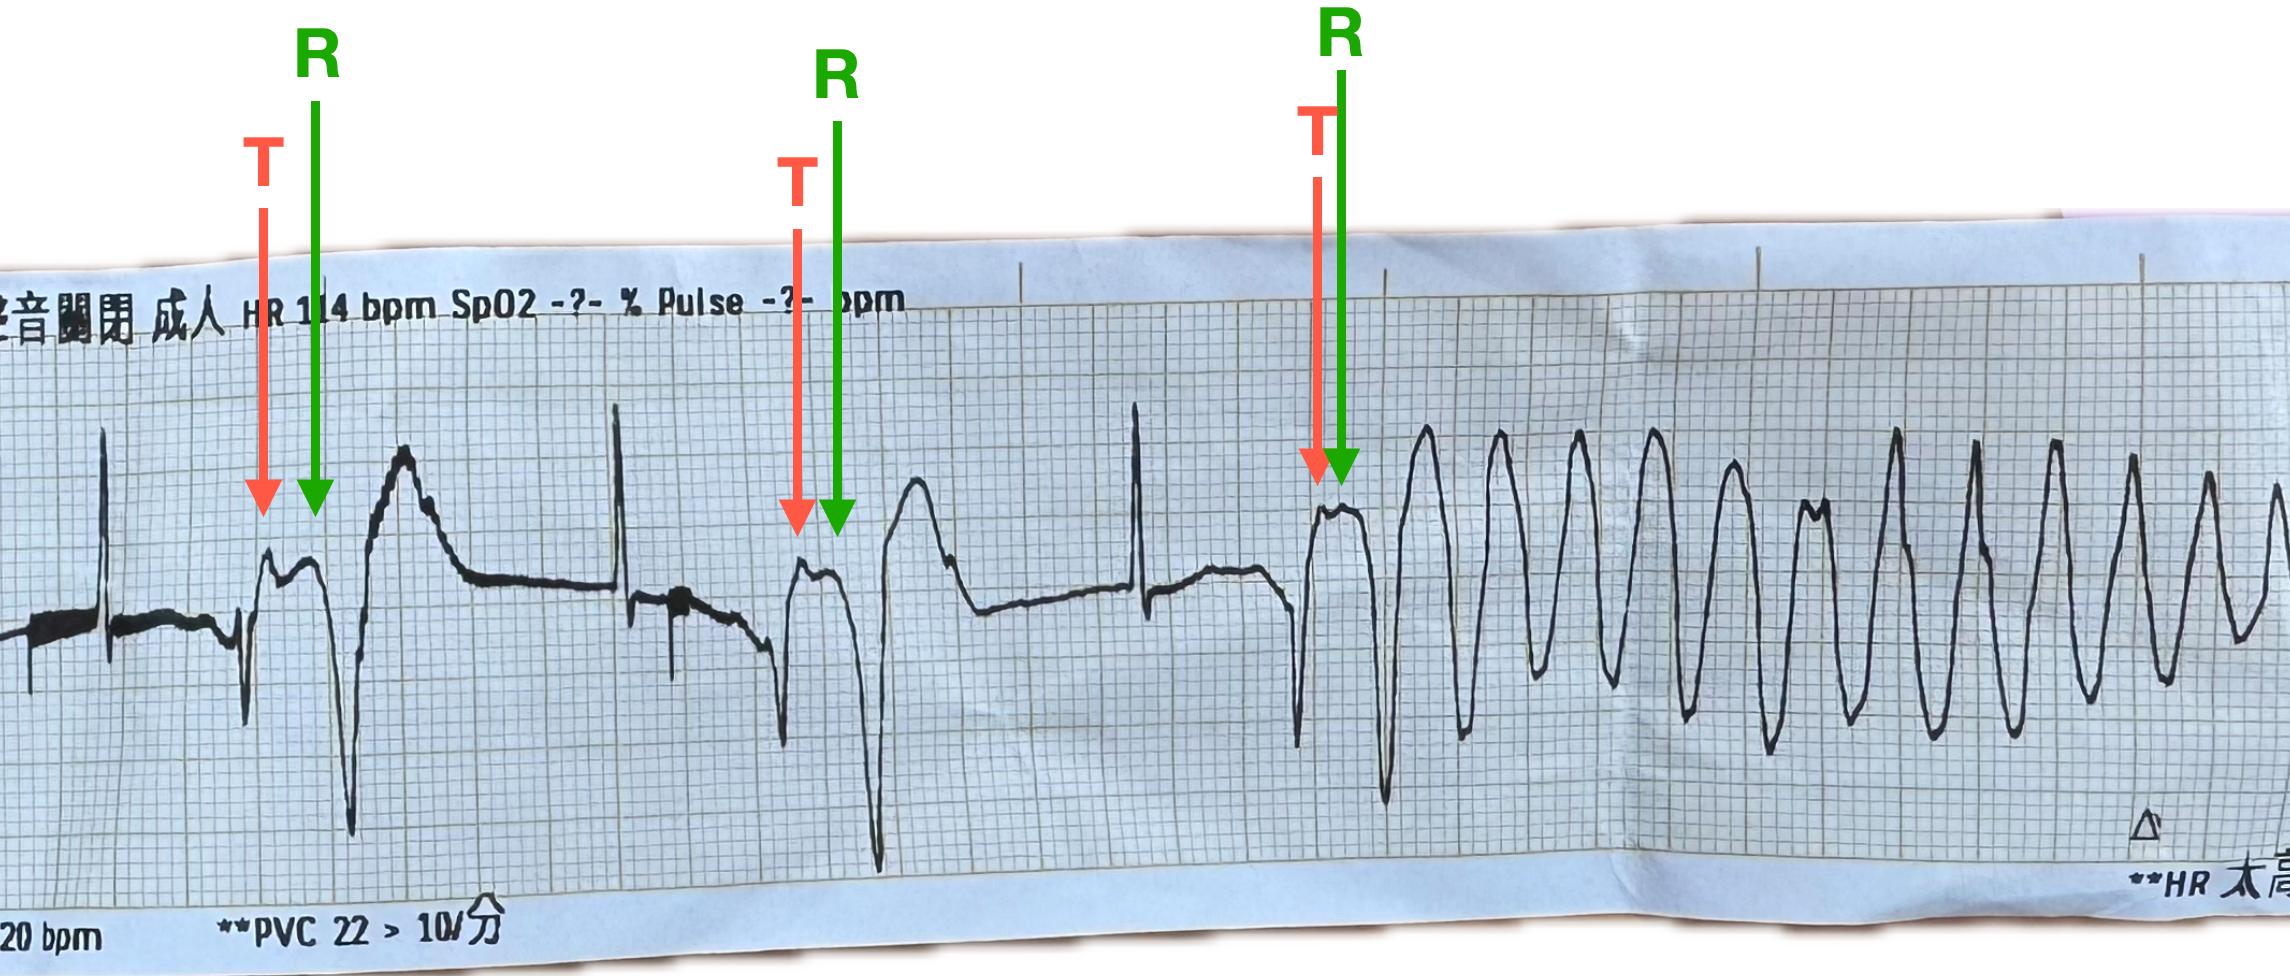

我把此Case因為跳R on T phenomenon產生心室性心律不整的ECG strip後半段拉出來看(Fig.11)。

老實說這到底是Vf還是跳polymorphic VT?

看rhythm像polymorphic VT(TdP type)的morphology。據護理師描述,當下沒有摸到脈搏。

有可能真的是Vf,或是因為polymorphic VT也算是一種惡性心室性心律不整,導致這病患的cardiac output變很差,也幾乎讓病患要摸不到脈搏了。

不管如何,病患如果不穩定,就還是得先電矯正心律再說。